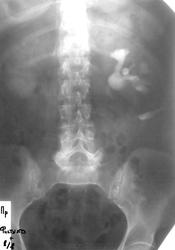

Женщина средних лет. 8 месяцев назад - пиелолитотомия слева по поводу МКБ. Свищ слева  по наружной поверхности боковой стенки живота в мезогастрии.

Проведена В\в урография с дополнением фистулографией на 120 мин.

По снимкам забрюшинное образование левой поясничной области с оттеснением мочеточника кнаружи. Сказать, имеется ли связь фистулы и ЧЛС затрудняюсь. Очень вероятен вазо-ренальный конфликт и пиелокаликоэктазия слева. Возможно, имело смысл провести фистулографию в другой день. Справа вероятны синусовые кисты.

Но вот вопрос - оттеснение наружу...или оттягивание наружу?)))))...а это важно....

Думаю, что всё-таки огибает какое-то образование. Если бы оттягивало не было такого ровного контура.